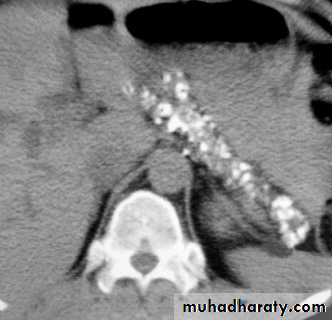

CT scan: chronic pancreatitis with marked calcification of the pancreatic parenchyma.